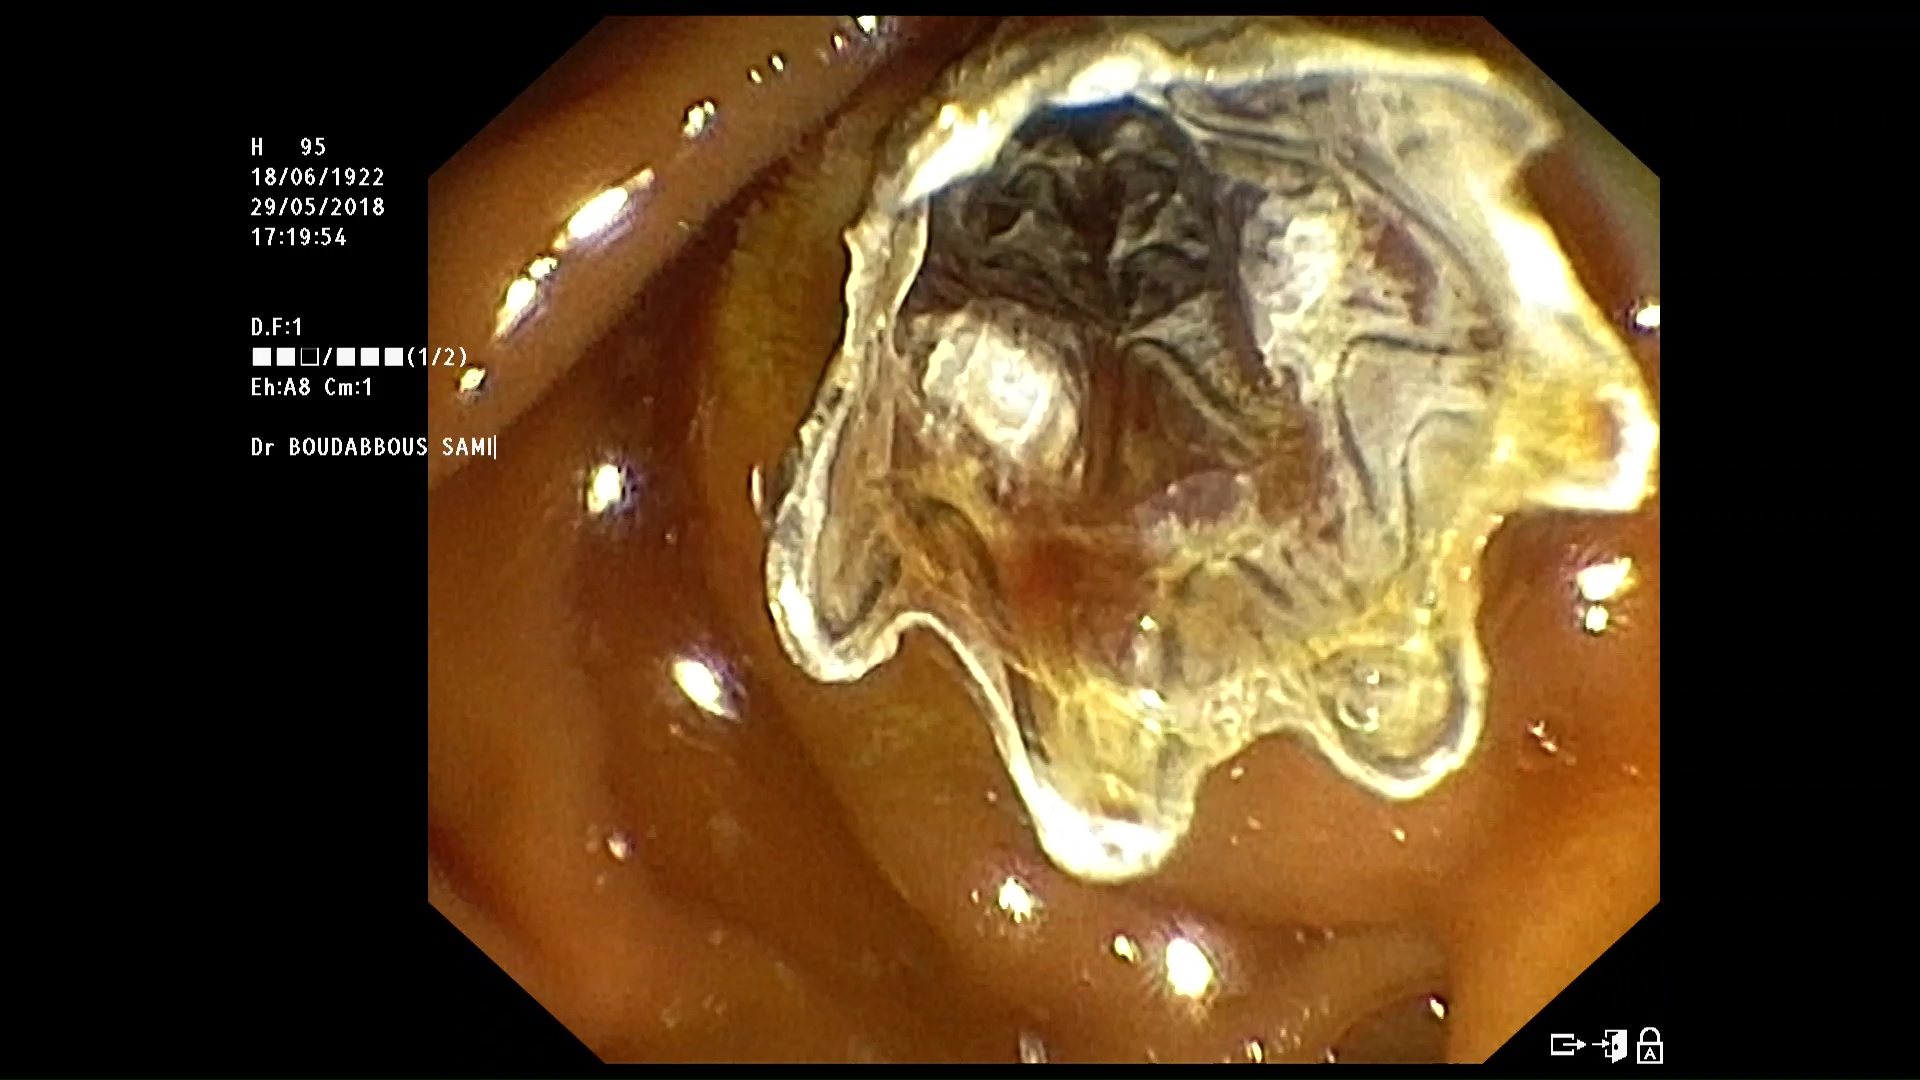

Prothèse biliaire en place